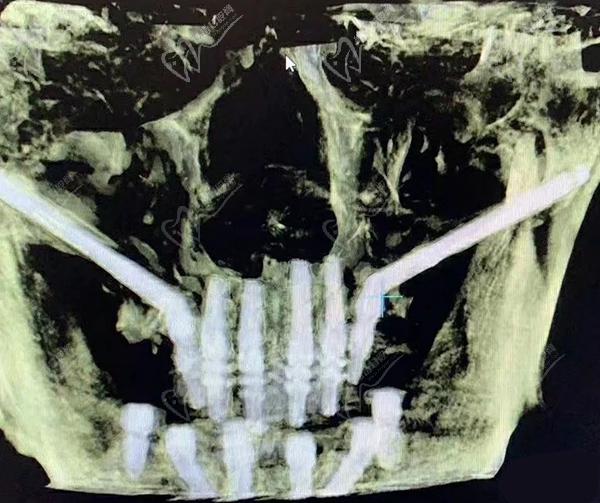

第三步:种植牙

接下来,医生会在必要的位置上植入种植体。这些种植体充当人工牙根,用于支撑和固定新的牙齿。采用数字化智能种植技术,上下牙颌各仅需要4-6颗植体就能恢复半口牙14颗牙齿。